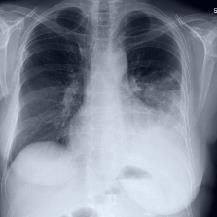

Thoracic disease detection from chest radiographs using deep learning methods has been an active area of research in the last decade. Most previous methods attempt to focus on the diseased organs of the image by identifying spatial regions responsible for significant contributions to the model's prediction. In contrast, expert radiologists first locate the prominent anatomical structures before determining if those regions are anomalous. Therefore, integrating anatomical knowledge within deep learning models could bring substantial improvement in automatic disease classification. This work proposes an anatomy-aware attention-based architecture named Anatomy X-Net, that prioritizes the spatial features guided by the pre-identified anatomy regions. We leverage a semi-supervised learning method using the JSRT dataset containing organ-level annotation to obtain the anatomical segmentation masks (for lungs and heart) for the NIH and CheXpert datasets. The proposed Anatomy X-Net uses the pre-trained DenseNet-121 as the backbone network with two corresponding structured modules, the Anatomy Aware Attention (AAA) and Probabilistic Weighted Average Pooling (PWAP), in a cohesive framework for anatomical attention learning. Our proposed method sets new state-of-the-art performance on the official NIH test set with an AUC score of 0.8439, proving the efficacy of utilizing the anatomy segmentation knowledge to improve the thoracic disease classification. Furthermore, the Anatomy X-Net yields an averaged AUC of 0.9020 on the Stanford CheXpert dataset, improving on existing methods that demonstrate the generalizability of the proposed framework.